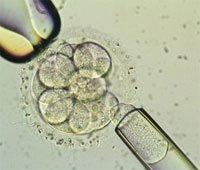

What is ICSI?

Intracytoplasmic sperm injection (ICSI) is an advanced IVF process in which a selected healthy sperm is injected directly into ovum simulating the natural process but in entirely controlled environment by a very advanced micro injector. Your IVF partner “KILKARI” is equipped with the latest imported ICSI machine with smoothest micromanipulators to ensure gentle handling of the delicate ova and sperm, this brings world class cutting edge IVF treatment to your door steps. We also believe that the man behind the machine is very important and hence the most experienced embryologists complete the procedure. Intracytoplasmic sperm injection (ICSI) is an advanced IVF process in which a selected healthy sperm is injected directly into ovum simulating the natural process but in entirely controlled environment by a very advanced micro injector. Your IVF partner “KILKARI” is equipped with the latest imported ICSI machine with smoothest micromanipulators to ensure gentle handling of the delicate ova and sperm, this brings world class cutting edge IVF treatment to your door steps. We also believe that the man behind the machine is very important and hence the most experienced embryologists complete the procedure.

What is the Procedure for ICSI?

ICSI is done as a part of IVF treatment. ICSI is done in the lab by special ICSI machine.

As with regular IVF, you’ll be given ovarian stimulating drugs, while your doctor will monitor your progress with blood tests and ultrasound. Once you’ve grown enough good-sized follicles, you’ll undergo the egg retrieval, where eggs are removed from your ovaries with a specialized, ultrasound-guided needle.

Your partner will provide his sperm sample that same day (unless you’re using a sperm donor, or previously frozen sperm.)

Once the eggs are retrieved, an embryologist will place the eggs in a special culture, and using a microscope and tiny needle, a single sperm will be injected into an egg. This will be done for each egg retrieved.